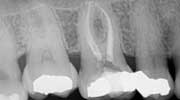

Second visit The patient returned to City Endodontics for treatment asymptomatic two weeks later. Rubber dam isolation and access were modified with the DOM; exploration of the distal anatomy was revisited. The distal canal was troughed with a fine diamond tip from an ultrasonic machine (Coltene), and a disto-buccal (DB2) canal located with the aid of the NaOCl 6% bubble test and anatomical landmarks. The DB2 canal was cleaned and shaped to length using same technique used for the other canals at the initial visit. The apex locator Root ZX II was used to confirm presence of an additional canal and reconfirm length for other canals. A check film was taken with files in all five canals to verify presence of five separate orifices and apices. A master cone for all five canals with gutta percha fit to working length was exposed. (Fig. 3)Fig. 3: Master cone fit radiograph of tooth No. 3 highlighting five canals